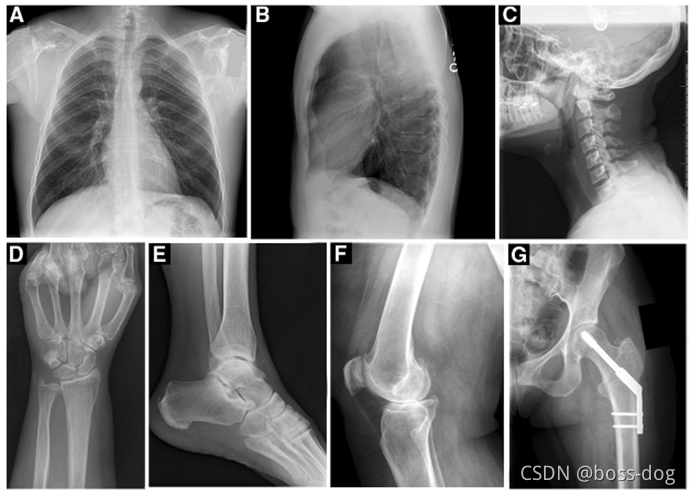

Radiography(X光成像)

上图中:

A和B两张都是胸透的片子,但就是X光穿过人体的位置方式不一样。

A是从前往后或者是从后往前这么照的;

B是侧着从左往右或者是从右向左这么照的;

C是颈椎(Lateral cervical spine)的成像,也是从左往右或者是从右向左这么照的;

D是手腕(Wrist)的成像,可以看清楚腕关节;

E是脚踝(Ankle)成像;

F是膝关节(Knee)成像;

G是髋关节(Hip)成像(里面还有一些金属的物体(钛合金)用来固定髋关节骨头);

综上可知X光看骨骼比较清除,比如一些骨折通过拍X光或者胸透。